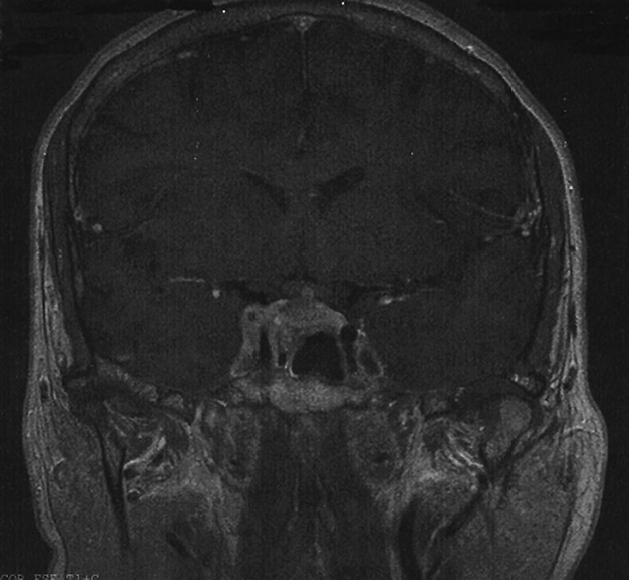

Mujer de 51 años de edad, fumadora de 20 paquetes/año, con antecedentes personales de intervención quirúrgica por gangrena de Fournier hace 20 años y menopausia hace 1 año. Sin antecedentes familiares de interés. Inicia de forma súbita clínica de polidipsia de hasta 10 litros al día junto con poliuria y nicturia. Un mes más tarde comienza con diplopía binocular, hemianopsia bilateral, cefalea y ptosis completa del párpado superior del ojo derecho. Ante la clínica referida es derivada a Oftalmología para valoración, solicitando por su parte una Resonancia Magnética cerebral que se informa como voluminoso macroadenoma hipofisario que invade el seno cavernoso derecho (Figura 1).

Figura 1. Resonancia Magnética que demuestra macroadenoma hipofisario que invade el seno cavernoso derecho.